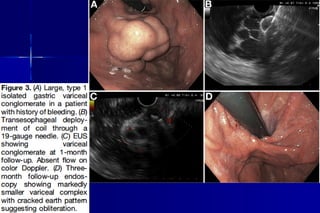

 GV bleeding: less common but present in up to 20% withGV bleeding: less common but present in up to 20% with

PHT.PHT.

 65% of GV present with bleeding over 2 years.65% of GV present with bleeding over 2 years.

 Direct endoscopic CYA inj of bleeding GV, widely consideredDirect endoscopic CYA inj of bleeding GV, widely considered

first-line therapy with hemostasis 58–100%& recurrentfirst-line therapy with hemostasis 58–100%& recurrent

bleeding 0%–40%.bleeding 0%–40%.

 The most serious adverse event is systemic embolization,PEThe most serious adverse event is systemic embolization,PE

in 58% ,Sepsis, Embolization into the artery (via PFO or AVin 58% ,Sepsis, Embolization into the artery (via PFO or AV

pulmonary shunt) result in stroke&multiorgan infarction.pulmonary shunt) result in stroke&multiorgan infarction.

 Factors increase the embolization: overdilution with lipiodol,Factors increase the embolization: overdilution with lipiodol,

excessively rapid inj, inj of too large a volume in a singleexcessively rapid inj, inj of too large a volume in a single

inj& isolated GV type 1 that have high blood-flow rates.inj& isolated GV type 1 that have high blood-flow rates.

 EUS-guided CYA inj or +coil used for effective hemostasis.EUS-guided CYA inj or +coil used for effective hemostasis.

 Delivery of CYA under EUS guide has advantage of enablingDelivery of CYA under EUS guide has advantage of enabling

precise delivery of glue into varix lumen&enablesprecise delivery of glue into varix lumen&enables

assessment with Doppler to confirm vessel obliteration afterassessment with Doppler to confirm vessel obliteration after

trt with prognostic significance, as recurrent bleeding risktrt with prognostic significance, as recurrent bleeding risk

linked to residual patency of treated varices.linked to residual patency of treated varices.